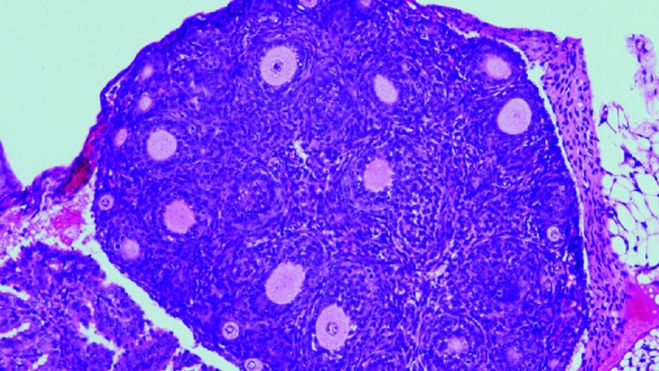

Un equipo del Centro de Investigación del Cáncer de Salamanca (CSIC-USAL) ha demostrado en un modelo de ratón el papel clave que cumple la mutación genética de un solo gen en la iniciación y desarrollo de los tumores de células granulosas de adulto (AGCT), un tipo de cáncer de ovario. Los resultados, que aparecen publicados en la revista Cancer Research, ayudan a comprender la naturaleza y los mecanismos moleculares del gen que codifica la proteína FOXL2, el cual está relacionado con la mayoría de estos tumores.

Cuando el óvulo se prepara para ser liberado en la ovulación, las células de la granulosa que lo rodean secretan un líquido folicular que crea una cavidad o antro. Esta masa de tejido, líquido y óvulo, recibe el nombre de folículo de Graaf. Los tumores de células de la granulosa de adulto (AGCT) son el tipo más común de tumores no epiteliales del ovario. Los AGCT ocurren con mayor frecuencia después de la menopausia y tienen un pronóstico favorable. Las recurrencias agresivas, a menudo fatales, pueden ocurrir hasta en el 50% de los casos diagnosticados. Como dichos tumores crecen lentamente, pueden reaparecer incluso 30 años después de la extirpación del tumor primario.

La mayor parte de los tumores sólidos se caracterizan por presentar varias mutaciones en diferentes genes (oncogenes o genes supresores), que son los responsables causales del desarrollo y progresión del cáncer. Mediante la secuenciación masiva del genoma de AGCTs, se ha determinado desde hace más de una década que una de las numerosas mutaciones presentes en sus genomas se localiza en el gen FOXL2 en más del 90% de este tipo de tumores. Cabe destacar que la mutación descrita es idéntica en todos los AGCTs secuenciados y consiste en una mutación puntual en el gen FOXL2. En concreto, se produce un cambio de la base citosina a guanina, que provoca la sustitución de un solo aminoácido de los 376 que constituyen la proteína completa FOXL2, esto es, cambia el aminoácido cisteína (C) de la posición 134 por un triptófano (W), denominado C134W.

“Nuestro grupo -señala Elena Llano, de la Universidad de Salamanca- ha desarrollado por primera vez un modelo de ratón que alberga en su gen FOXL2 la variante C134W, presente en los tumores humanos, para así poder evaluar in vivo el papel desconocido de FOXL2 en la iniciación y desarrollo tumoral. Para nuestra sorpresa, estos ratones presentan la hipoplasia del párpado observada en el síndrome de blefarofimosis. Curiosamente, las hembras con dicha mutación presentan una fertilidad reducida y lo que es más relevante todas desarrollan AGCT espontáneamente. Es decir, progresan gradualmente de ovarios anormales con células de la granulosa aberrantes a ovarios con hiperplasia estromal y atipia, que finalmente dan lugar a la aparición de tumores ováricos en la totalidad de los animales antes de los 18 meses de edad. Por tanto, este proceso parece estar impulsado únicamente por la presencia de la variante FOXL2”.

Pendás resalta: “Cuando comparamos estos datos con resultados previos en AGCTs humanos observamos vías desreguladas similares. Finalmente, un análisis mutacional de los datos transcriptómicos de los AGCTs del ratón sugirió la ausencia de mutaciones conductoras adicionales además de FOXL2-C134W. Estos resultados proporcionan un claro ejemplo in vivo en el que la mutación de un solo gen desencadena el desarrollo de un tumor con profundas alteraciones en la expresión de numerosos genes cruciales para la homeostasis normal del ovario”.